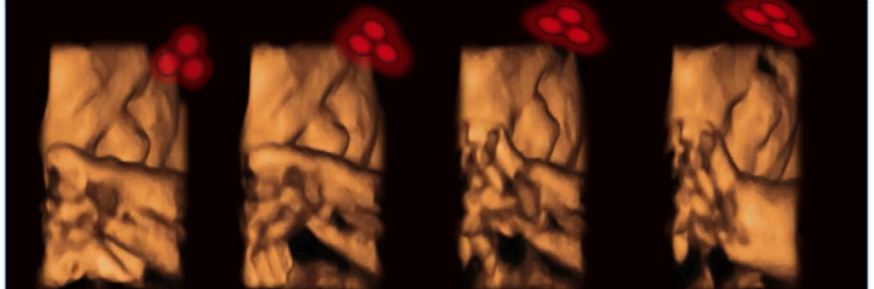

The team used a light source to project a pattern of three dots in the shape of eyes and a mouth through the uterine wall and measured the way the foetus responded using ultrasound.

The findings show that foetuses of 34 weeks gestation will turn their head to track the face-like pattern.

But there was no such movement when the team projected three inverted dots in the shape of a triangle, demonstrating that it was not the pattern itself which the foetus preferred.